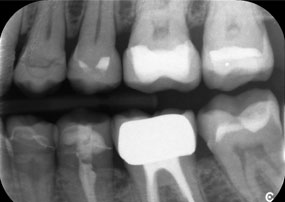

Le défi consistait à retirer douze couronnes splintées en alliage métallique sans endommager les dents piliers sous-jacentes. La pièce à main a été utilisée pour sectionner avec précision les couches de céramique et diviser l'armature métallique à l'aide d'une fraise au carbure, ce qui a permis un retrait minimalement traumatisant des couronnes. En seulement 30 minutes, les anciennes restaurations ont été retirées, permettant la préparation d'une nouvelle prothèse, composée de zircone à contour complet dans la région postérieure et de couronnes facettées dans la région antérieure. Le résultat a été une restauration complète qui a permis d'obtenir un succès tant fonctionnel qu'esthétique (voir fig. 1).

Radiographie de la mâchoire d'un patient âgé de 81 ans, sur fond noir.

Figure 1 : Réhabilitation esthétique des couronnes PFM : retrait complet et remplacement des couronnes PFM vieilles de 40 ans afin d'améliorer l'esthétique chez un patient âgé de 81 ans.